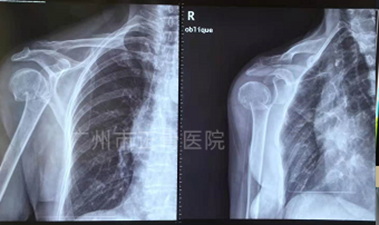

治疗:手法复位小夹板外固定治疗。手法复位后复查X片见骨折位线好。嘱患者定期复查(每周一次),指导患者循序渐进进行手指、腕部及肘关节功能锻炼。6周后复查X线提示骨折对位对线良好,骨痂生长,骨折线模糊,予拆除夹板,指导患者加强肩关节功能康复锻炼。8周后复诊,患者肩关节活动恢复正常。

▲6周后X线,骨折端对位对线良好,骨折线模糊